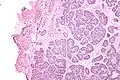

| Micrograph of a Sertoli cell nodule. H&E stain. | |

Sertoli cell nodules are unencapsulated nodules that consist of:[1][2][3]

- cells arranged in well-formed tubules (that vaguely resemble immature Sertoli cells), with

- bland hyperchromatic oval/round nuclei that are stratified, and

- may contain eosinophilic (hyaline) blob in lumen (centre).

Micrograph of a Sertoli cell nodule. H&E stain.